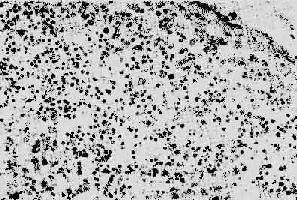

1. 淋巴样组织的变化早期及中期,淋巴结肿大。镜下,最初有淋巴滤泡明显增生,生发中心活跃,髓质出现较多浆细胞。随后滤泡的外套层淋巴细胞减少或消失,小血 管增生,并有纤维蛋白样物质或玻璃样物质沉积,生发中心被零落分割。副皮质区的淋巴细胞(CD4+细胞)进行性减少,代之以浆细胞浸润晚期淋巴结病 变,往往尸检时才能看到,呈现一片荒芜,淋巴细胞,包括T、B细胞几乎均消失殆尽,无淋巴滤泡及副皮质区之分,仅有一些巨噬细胞和浆细胞残留(图 4-15)。有时特殊染色可显现大量分枝杆菌、真菌等病原微生物,却很少见到肉芽肿形成等细胞免疫反应性病变。

AIDS淋巴结

图4-15 AIDS淋巴结

淋巴细胞明显减少,无淋巴滤泡及副皮质区之分